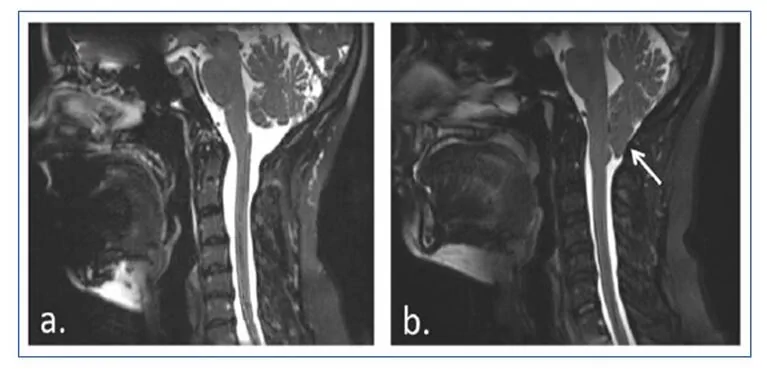

هو تشوه ناتج عن تطور غير كامل للجزء الخلفي السفلي من قاعدة الجمجمة خلال الفترة الجنينية، والذي قد يصاحبه مضاعفات مثل السيرنغوميليا والاستسقاء الدماغي.

أقصى صورة منه تتمثل في هبوط أجزاء من أدنى جزء من المخيخ، اللوزات المخيخية ، وكذلك جذع الدماغ عبر الثقب القذالي الكبير، بحيث تصل بعض أجزاء الدماغ إلى القناة الشوكية مما يؤدي إلى تضخّمها وضغطها.

تشوه كياري من النوع الأول ينطوي على فتق سفلي للّوزات المخيخية بقدر يقارب 5 ملم أسفل الثقب القذالي الكبير، والذي عادةً لا يصاحبه هبوط لجذع الدماغ أو البطين الرابع ولا الاستسقاء الدماغي، لكنه غالبًا ما يصاحبه السيرنغوميليا.

تتسبب السيرنغوميليا بتكوّن تجاويف أو أكياس (سيرنك أو syrinx) مملوءة بسائل داخل الحبل الشوكي، والتي قد تتوسع ببطء، محدثة ضررًا تدريجيًا للحبل الشوكي وارتفاع ضغط داخل القحف بسبب الضغط الذي يسببه ذلك السائل.

فتاة تم تشخيصها بتشوه كياري من النوع الأول مصحوبًا بسيرنغوميليا، خضعت لتدخل جراحي عند بلوغها 12 عامًا.